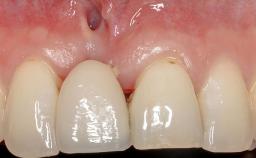

Treatment of Soft-Tissue Fenestration in the Esthetic Zone

This case demonstrates that a connective-tissue graft in combination with a coronally positioned graft is an effective method of treating cases with peri-implant mucositis and an abutment-level sinus abscess. A 42-year-old man presented with a swelling adjacent to an implant crown at site 21. The swelling had been present for approximately three weeks and was constrained to the buccal and palatal gingival aspects of the implant. A discharge was noted on finger pressure, with localized gingival recession present on the mid- and distolabial aspects of the crown.